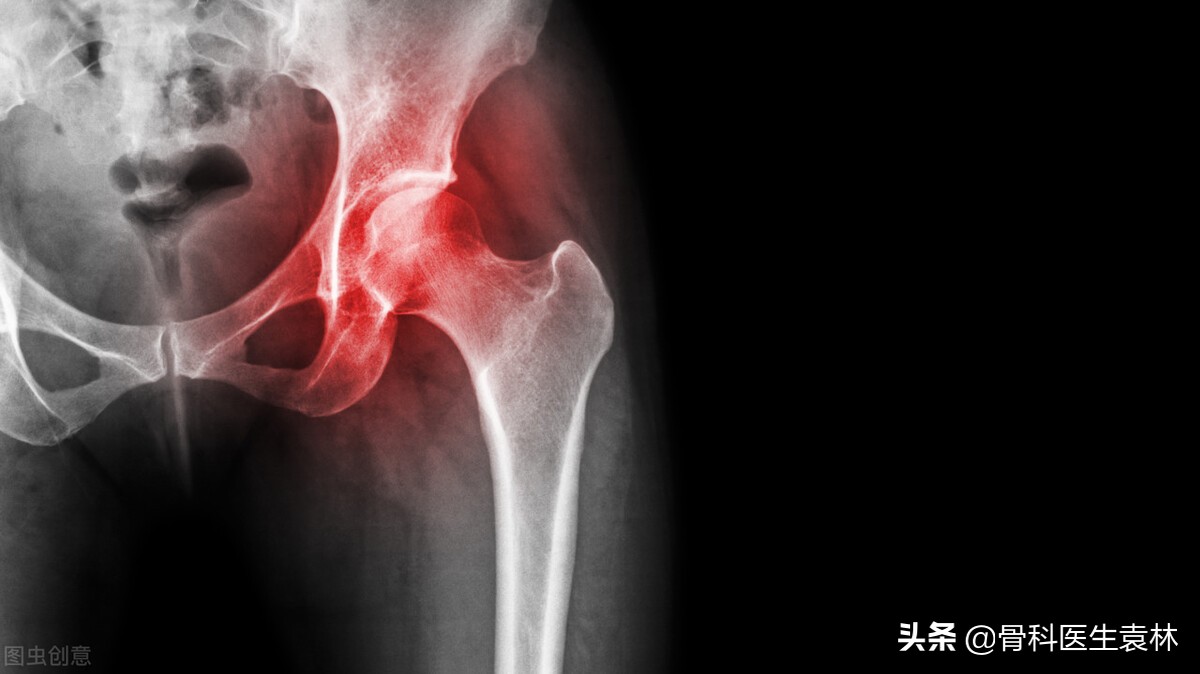

股骨头坏死又称股骨头缺血性坏死,系指股骨头血供受损或中断,导致骨髓成分结构改变及骨细胞死亡,而其后的自体修复导致股骨头结构改变,继而引起股骨头塌陷和功能障碍的疾病。

股骨头坏死到了晚期的时候,由于髋关节的严重病变,骨软骨塌陷等,患者的肢体活动范围会受到严重的限制,个别严重的患者甚至是失去行动能力而成为残疾患者。这时候如果及时的治疗还有站起来的希望,但如果一直拖延下去,当整个髋关节都坏死以后,除非使用假肢代替,否则只能是终生残疾。

人工关节置换术对治疗股骨头骨坏死效果较好,但由于术后出现一些并发症:如感染,股骨上端劈裂,假体移动或下沉等,而且一旦手术失败,再无其他手术可以补救,所以对该手术的适应证应从严掌握。

对III期以前的股骨头无菌性坏死,塌陷明显,甚至继发有骨关节炎者,也就是坏死较重,接近IV期者或VI期者方考虑手术治疗。